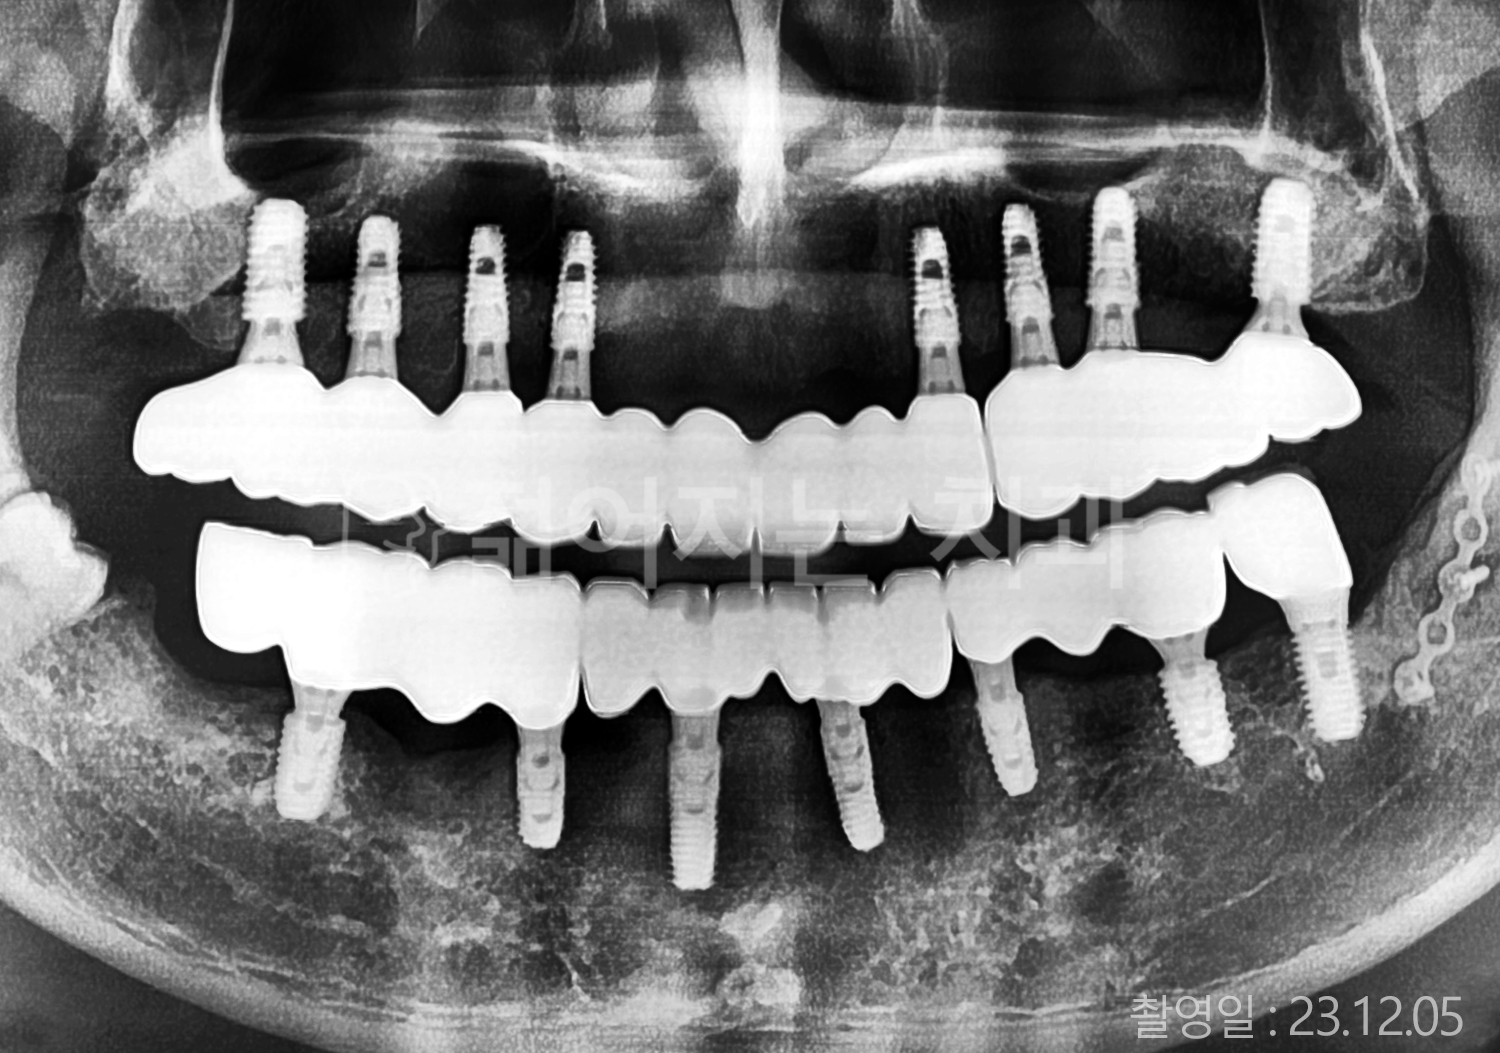

• 50대 고혈압, 당뇨, 고지혈증 전체치아 10개 이상 임플란트

• 50대 고혈압, 당뇨 전체치아 10개 이상 임플란트